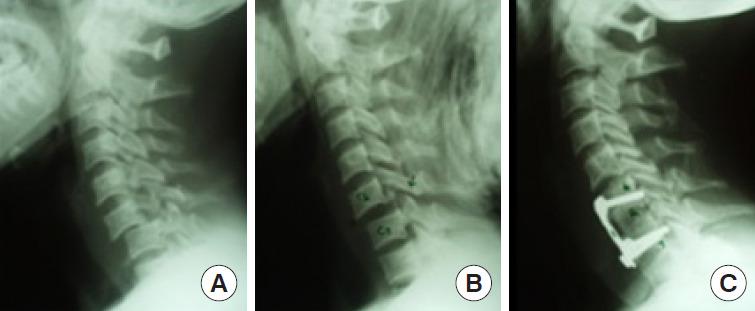

To formulate specific guidelines for the recommendation of subaxial cervical spine injuries concerning classification, management, posttraumatic locked facets and vertebral artery injury. Computerized literature was searched on PubMed and google scholar database from 2009 to 2020. For classification, keywords "Sub Axial Cervical Spine Classification," resulting in 22 articles related to subaxial cervical spine injury classification system (SLICS) system and 11 articles related to AO (Arbeitsgemeinschaft für Osteosynthesefragen, German for "Association for the Study of Internal Fixation") Spine system. The literature search yielded 210 and 78 articles on "management of subaxial cervical spine injuries" and the role of "SLICS" and "AO Spine" respectively. Keywords "management of traumatic facet locks" were searched and closed reduction, traction, approaches and techniques were studied. "Vertebral artery injury and cervical fracture" exhibited 2,328 references from the last 15 years. The objective was to identify the appropriate diagnostic tests and optimal treatment. Up-to-date information was reviewed, and statements were produced to reach a consensus in 2 separate consensus meetings of World Federation of Neurosurgical Societies (WFNS) Spine Committee. The statements were voted and reached a positive or negative consensus using Delphi method. Based on the most relevant literature, panelists in Moscow consensus meeting conducted in May 2019 drafted the statements, and after a preliminary voting session, the consensus was identified on various statements. Another meeting was conducted at Peshawar in November 2019, where in addition to previous statements, few other statements were discussed and voted. Specific recommendations were then formulated guiding classification, management, locked facets and vertebral artery injuries. This review summarizes the WFNS Spine Committee recommendations on subaxial cervical spine injuries.

制定关于下颈椎损伤的分类、管理、创伤后小关节交锁和椎动脉损伤推荐的具体指南。在PubMed和谷歌学术数据库中检索2009年至2020年的计算机化文献。对于分类,关键词“下颈椎分类”,检索到22篇与下颈椎损伤分类系统(SLICS)相关的文章以及11篇与AO(德语“骨内固定研究协会”,即“内固定研究协会”)脊柱系统相关的文章。文献检索分别产生了210篇和78篇关于“下颈椎损伤的管理”以及“SLICS”和“AO脊柱”作用的文章。检索关键词“创伤性小关节交锁的管理”,并研究了闭合复位、牵引、入路和技术。“椎动脉损伤与颈椎骨折”在过去15年中有2328条参考文献。目的是确定合适的诊断测试和最佳治疗方法。回顾了最新信息,并在世界神经外科协会联合会(WFNS)脊柱委员会的2次单独共识会议上达成共识声明。这些声明采用德尔菲法进行投票,并达成肯定或否定的共识。基于最相关的文献,2019年5月在莫斯科举行的共识会议的专家小组成员起草了声明,在初步投票会议后,就各项声明达成了共识。2019年11月在白沙瓦举行了另一次会议,除了之前的声明外,还讨论并投票了其他一些声明。随后制定了关于分类、管理、小关节交锁和椎动脉损伤的具体建议。本综述总结了WFNS脊柱委员会关于下颈椎损伤的建议。